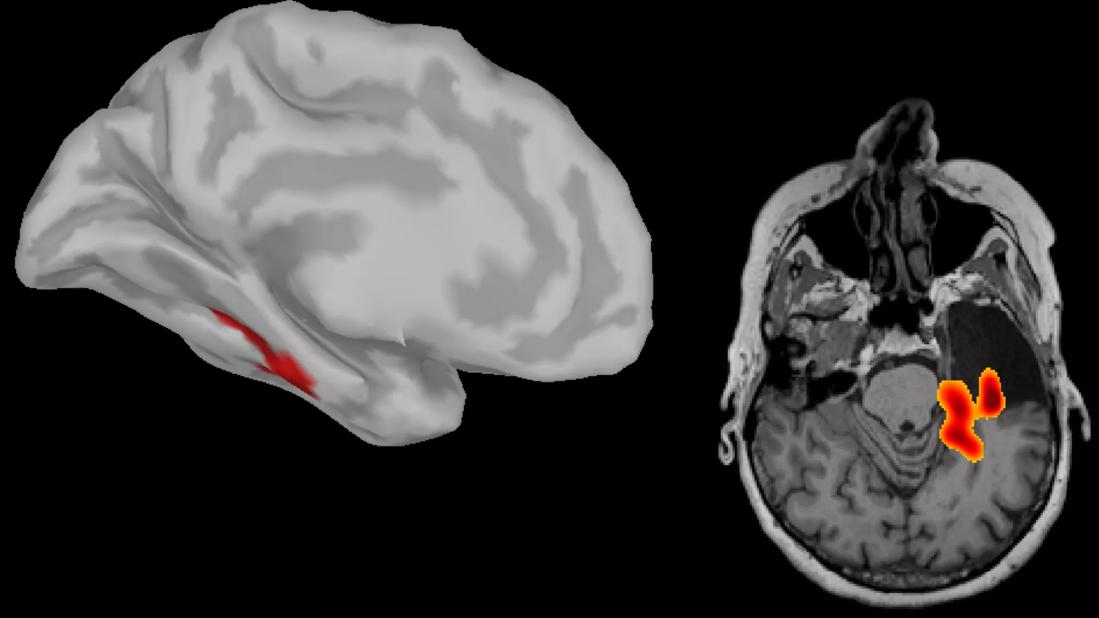

The figure below shows the net information exchange into (panel A) and out of (panel B) insular cortex across 22 patients. Panel C shows findings from a patient who underwent right temporal lobectomy. A high asymmetry index in network centrality can be observed in the left mesial temporal lobe. Panel D presents an example of where a high asymmetry index in network centrality was observed in the right middle frontal gyrus and the left lingual area (not shown). This patient underwent resection of the right middle frontal gyrus and has been seizure-free.

Figure. Average information exchange map for insular cortex across 22 patients. Panel A shows net information exchange to insula from other cortical regions, whereas panel B shows net information exchange from insula to other cortical regions. Panels C and D present illustrative examples of results of focus localization using resting-state connectivity analysis rendered of patients’ individual cortex and postoperative MRI. Panel C shows a case of temporal lobe epilepsy in which high connectivity was observed in the left hippocampal formation. The patient underwent left temporal lobectomy. Panel D shows a case of frontal lobe epilepsy in which high connectivity was observed in the left lingual (not shown) and right middle frontal gyrus. The patient underwent resection of the right middle frontal gyrus and has been seizure-free. See text for additional discussion.